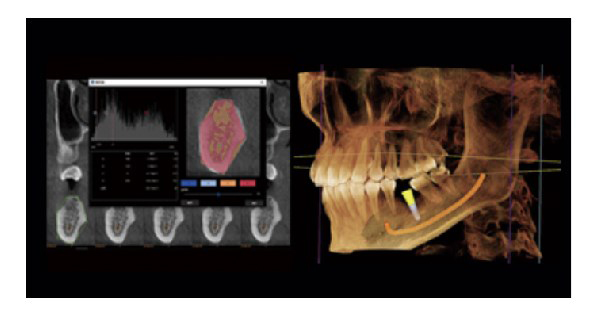

- Autosegmentación de dientes y marcación automática de canal mandibular

La IA inteligente permite un diagnóstico y una planificación de planes de tratamiento más precisos.

Segmentación dental automática.

Planificación de la cirugia de implantes

Representación del tubo neural

- Comprobar la dirección del tubo neural y su relación con la posición de las muelas del juicio

- Comprobar la distancia entre el tubo neural y el implante para evitar que el implante toque el tubo neural

Siembra simulada

- DViewMatrix ha agregado un nuevo modulo de implante de simulación 30, que puede medir el ancho, la altura y la densidad ósea de los dientes faltantes y el hueso alveolar, y también puede realizar la delineación del tubo neural.

- Rica biblioteca de implantes

- Introducir parametros de implante simulados y diseñar un plan de implante simulado.

Medición de la densidad ósea

- Medir la osteoporosis y proporcionar referencia para la implantaci6n.